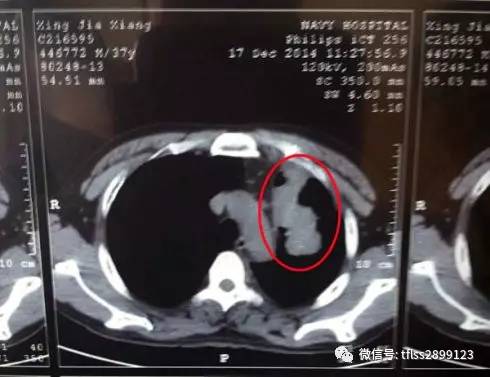

据报道,一位45岁的男性患者在常规体检中发现胆囊内有一枚约2厘米的结石,患者没有明显症状,医生建议定期复查,半年后,患者再次复查时发现,那枚结石已经消失了。

这一案例被医生称为"罕见事件",虽然具体原因尚不完全明确,但专家提出了几种可能的解释: